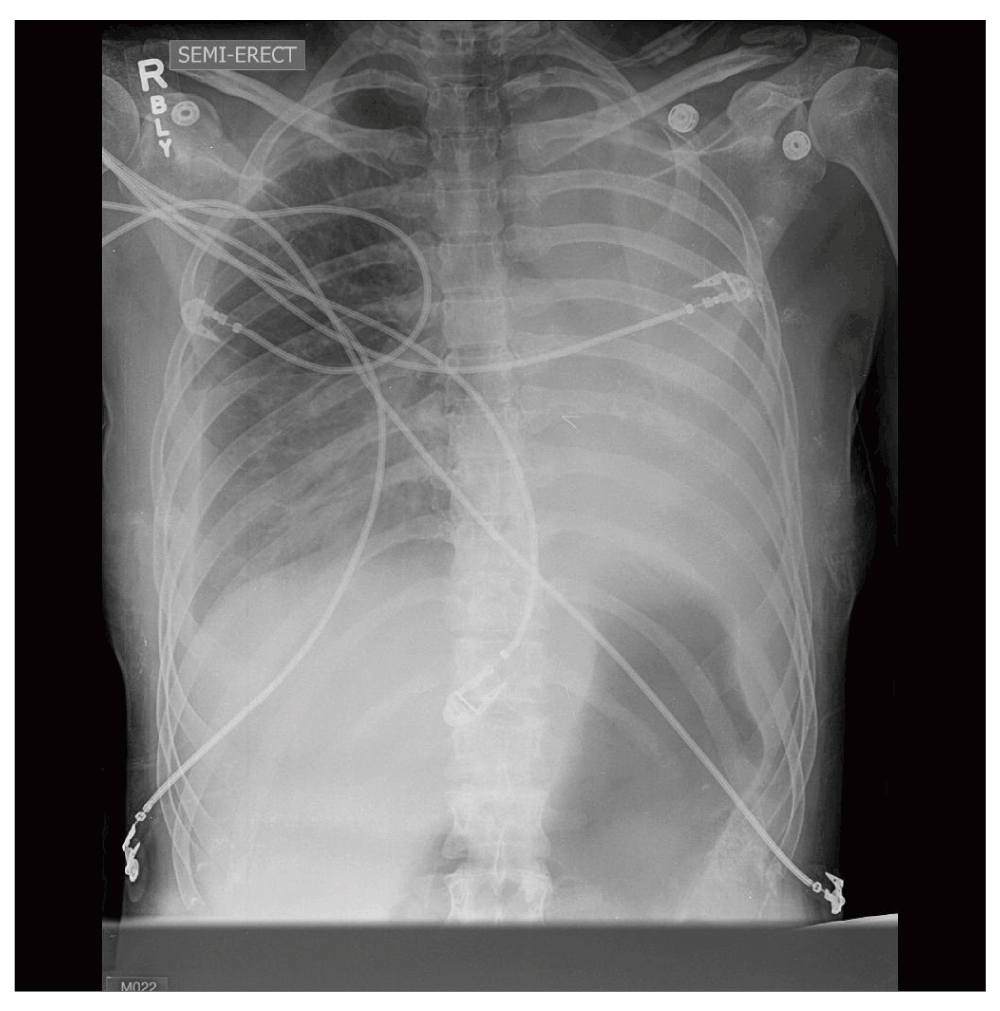

Chest radiographs in pregnancy The BMJ

Abnormal chest radiograph in pregnancy The BMJ Can A Chest X Ray Affect Pregnancy In fact, the american college of obstetricians and gynecologists (acog). He says that in pregnant women who are beyond. this document reviews the safety and effectiveness of various imaging modalities for pregnant and lactating women and. Yes, you can, as long as it isn't of your belly, which would expose your baby. Can A Chest X Ray Affect Pregnancy.